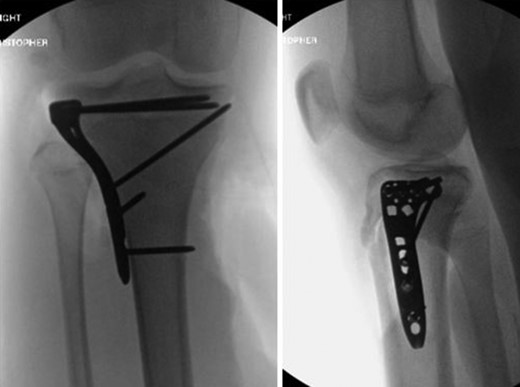

AP and lateral intraoperative fluoroscopic images following ORIF with proximal tibial locking plate.